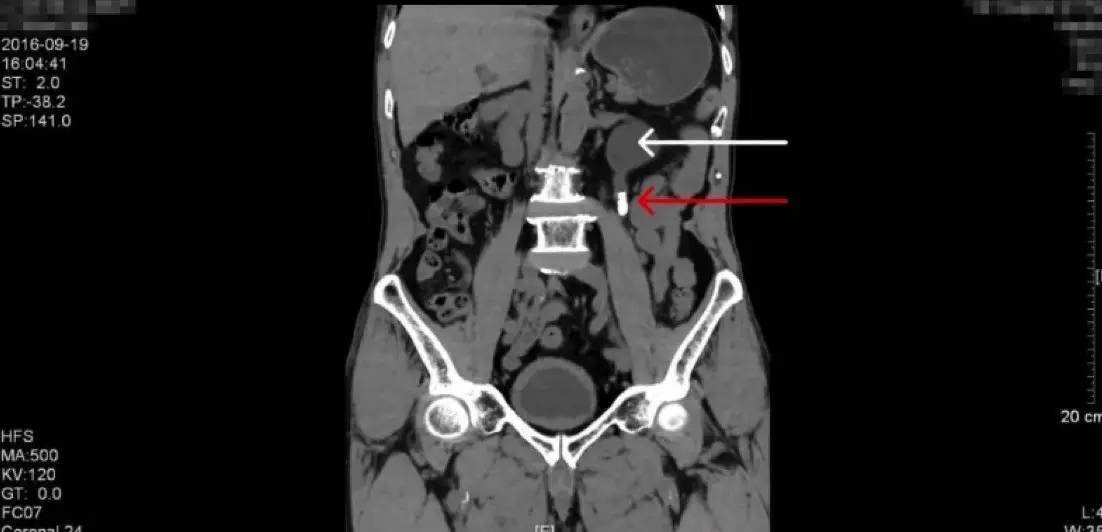

上图为CT平扫的三维重建图像(红色箭头为结石,白色箭头为积水肾)

泌尿系CT平扫是泌尿系结石手术前的必备检查,因为它能够清晰的显示各个器官的毗邻结构和结石的位置大小,并且能够做图像的三维重建。本例患者的CT图像如上,结石同样显示为白色强化,是身体的横截面,这里结石看起来是圆形的,是结石的横截面。